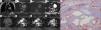

Pericardial hemangioma: MRI – (A) coronal T2-weighted imaging without fat saturation; (B) axial T2-weighted imaging with fat saturation; (C and D) diffusion-weighted imaging with ADC Map; (E–H) dynamic contrast-enhanced imaging – revealing a well-circumscribed mass (arrows) between the pulmonary trunk, the anterior wall of the left ventricle and the aortic root, with no signs of invasion of the surrounding structures; the mass is hyperintense in T2-weighted imaging (A and B), not showing diffusion restriction (C and D); after intravenous administration of gadolinium-based contrast media, the mass presents globular and centripetal enhancement (E–H). A diagnosis of pericardial hemangioma was proposed. Photomicrograph of hematoxylin-and-eosin-stained tissue of the surgical specimen (I) reveals several cavernous spaces filled with blood, corroborating the imaging diagnostic hypothesis of hemangioma.

MRI revealed a 5 cm well-circumscribed mass between the pulmonary trunk, the anterior wall of the left ventricle and the aortic root, not showing signs of invasion of the surrounding structures; it presented hyperintensity in T2-weighted sequences (Figure 1A and B) without diffusion restriction (Figure 1C and D), revealing globular and centripetal enhancement following intravenous administration of gadolinium-based contrast agent (Figure 1E–H). It was hypothesized that the mediastinal mass corresponded to a pericardial hemangioma.

The pathologic evaluation of the surgical specimen showcased several blood-filled cavernous spaces (Figure 1I), consistent with the diagnosis of hemangioma.